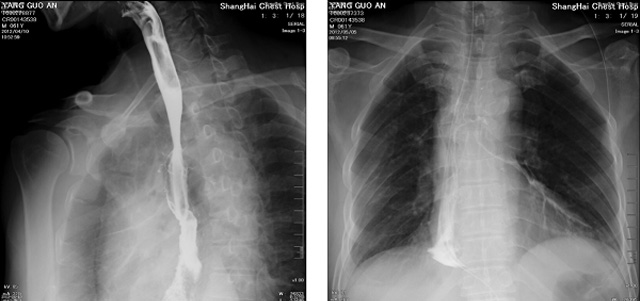

DR設(shè)備在2020年的新冠疫情中,加速了市場調(diào)整。以醫(yī)院為主的向二三級市場轉(zhuǎn)變。特別是小巧靈活的移動DR設(shè)計,填補CT和磁共振不能三維檢查的缺點,滿足內(nèi)科外科特別是骨科的影像診斷需求。還有懸吊DR設(shè)備CT斷層射線系統(tǒng)。使用錐束成像技術(shù)對整個脊柱和整個下肢進行了體積三維掃描。無需使用對比劑,即可使用X射線呼吸功能標(biāo)測來模擬模擬氣流和血流,以評估患者的肺動脈血栓。